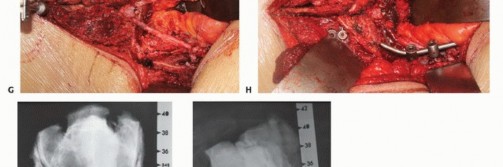

يقوم الأستاذ الدكتور محمد هطيف بتطبيق تقنيات جراحية متقدمة لضمان الاستئصال الآمن والفعال لأورام العجز، مع إيلاء اهتمام خاص للحفاظ على الأعصاب الحيوية.

استئصال ورم العجز عبر الوصول الأمامي الخلفي

يُوضع المريض في وضعية جانبية (وضعية البطن العجزية الجانبية المشتركة).

الوصول الأمامي: يتم إجراء شق مكبرني ممتد أولاً. من خلال هذا الشق، يتم استكشاف الفضاء خلف الصفاق عن طريق تشريح عضلات جدار البطن. يتم دفع محتويات البطن إلى الجانب المقابل من البطن، مع حماية الحالبين. ثم يتم كشف الشريان الأبهر البطني والأوعية الحرقفية والأوعية العجزية الوسطى. في معظم الحالات، يمكن استئصال الورم الشفاني بهذا الشق فقط. يقلل هذا الشق من خطر النزيف عن طريق ربط الشريان الحرقفي الداخلي من نفس الجانب وحجب الشريان الأبهر مؤقتًا.

الوصول الخلفي: يبدأ الشق الخلفي من الناتئ الشوكي القطني ويمتد إلى 3 سم فوق العصعص. يمكن تعديل الشق إلى شكل H عرضي أو Y. في حالة وجود خزعة مفتوحة سابقة، يجب عمل شق بيضاوي لاستئصال مسار الخزعة بالكامل مع الورم.

قطع العظم العجزي

يتم تحديد مستوى قطع العظم العجزي بدقة باستخدام الكي الكهربائي، بقياس المسافة بين العصعص والمستوى المخطط له قبل الجراحة. تُقطع عضلات الألوية الكبرى على بعد 1 سم من نقطة ارتباطها بالعجز. تُربط الأوعية الدموية في عضلات الألوية بعناية. تُفصل عضلات الظهر المنتصبة إذا لم تكن متورطة.

بعد قطع الأربطة من الجوانب الأمامية والجانبية للعصعص، يتم دفع الأنسجة الدهنية الصفراء الموجودة أمام العجز أماميًا لخلق مساحة لقطع ارتباطات عضلات قاع الحوض في العجز. ثم يتم قطع الرباط العجزي الحدبي والرباط العجزي الشوكي.

يتم بعد ذلك كشف العضلة الكمثرية. تُطبق شاشات مبللة في الفضاء أمام العجز لتشريح كبسولة الورم الكاذبة من المستقيم. بعد تقسيم الرفاء العصعصي الشرجي، يتم إجراء تشريح لطيف بالأصابع لمسافة قصيرة على السطح الأمامي للأمعاء حتى يتم الوصول إلى مستوى التش